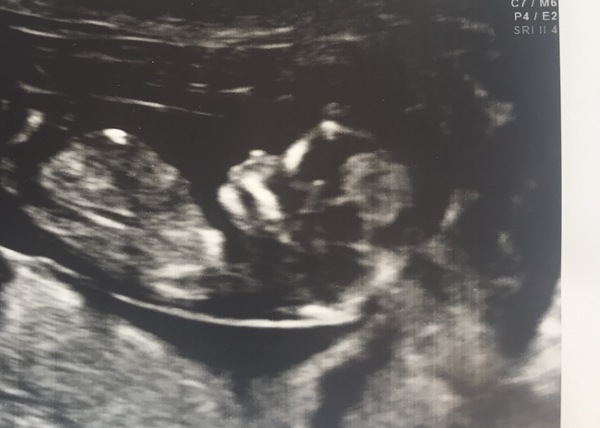

12+2. Due the 2nd April! Everything was perfect! 💛

Parney · 20/09/2017 20:57

So cute stars delighted all is well.

Yey great pic stars glad everything is perfect ☺️ X